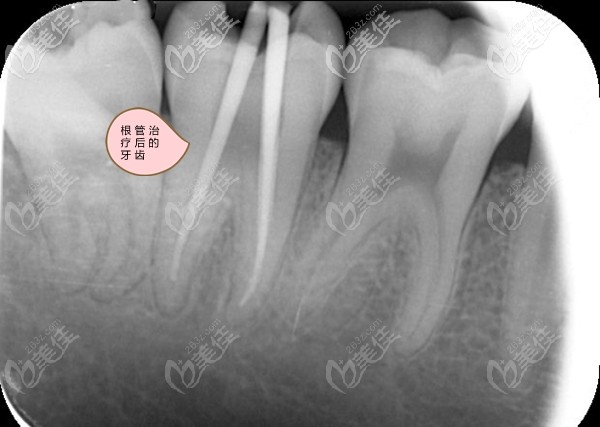

我第6磨牙的牙根彎曲做根管治療難度大嗎?

小區(qū)門(mén)口這家牙科診所的醫(yī)生,說(shuō)我的牙根彎曲根管治療通不開(kāi),讓我去大醫(yī)院的口腔科治療,我已經(jīng)拍了全景片,想請(qǐng)懂行的朋友幫我看看,是不是像我這種牙根彎曲難做根管治療呀。

事實(shí)上,磨牙的牙根80%以上都是彎的,相比直的牙根,治療起來(lái)難度肯定會(huì)增加,也很考驗(yàn)醫(yī)生的經(jīng)驗(yàn)和技術(shù)。好在現(xiàn)在有一種牙科顯微鏡設(shè)備,可以將牙齒的根管放大,還可以對(duì)口腔內(nèi)進(jìn)行補(bǔ)光,這樣大大增加了治療的便利性,效果也明顯提升。

對(duì)于彎曲度不是很大的牙根,只要不是狹窄、鈣化或是根分叉過(guò)多,也都是可以做完善的根管治療的,做那種顯微根管治療效果相對(duì)會(huì)更好些,不過(guò),許多小牙科目前都還沒(méi)有引進(jìn)這種設(shè)備和技術(shù)。